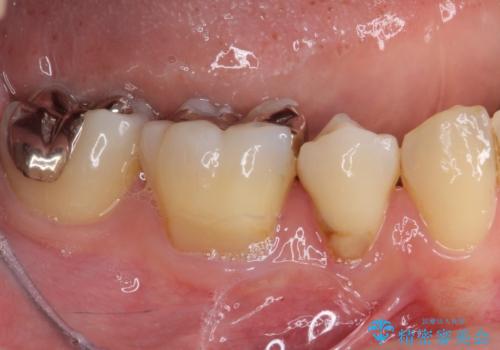

- 上下前歯の叢生を気にして来院された患者様です。

費用を抑え、期間もあまりかけずに治療をしたいとのことで、インビザライン・ライトを用いて矯正治療を行うこととしました。

矯正治療後には、下顎臼歯の目立つ銀歯をセラミックインレーにて修復治療を行いました。